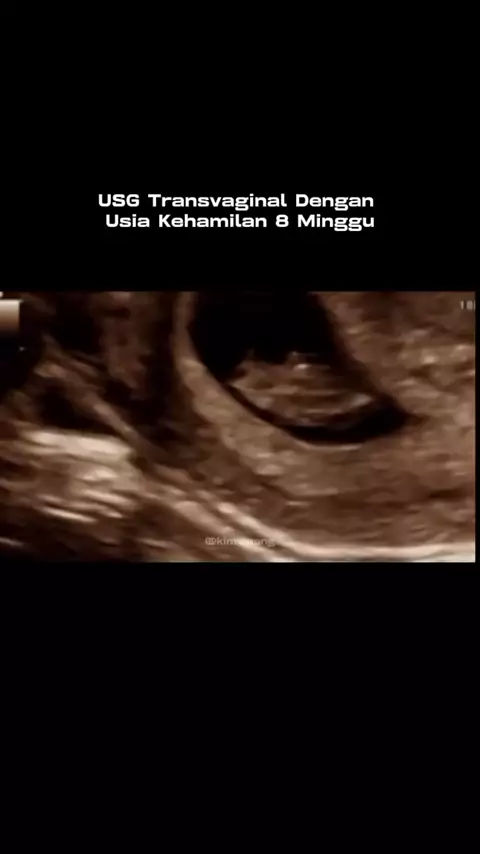

8 weeks pregnancy vaginal sonography